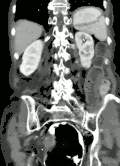

| Coronal CT of the abdomen, demonstrating a volvulus as indicated by twisting of the bowel stock | |

Risk factors include a birth defect known as intestinal malrotation, an enlarged colon, Hirschsprung disease, pregnancy, and abdominal adhesions.[1] Long term constipation and a high fiber diet may also increase the risk.[3] The most commonly affected part of the intestines in adults is the sigmoid colon, with the cecum being the second most affected.[1] In children the small intestine is more often involved.[5] The stomach can also be affected.[6] Diagnosis is typically with medical imaging such as plain X-rays, a GI series, or CT scan.[1]